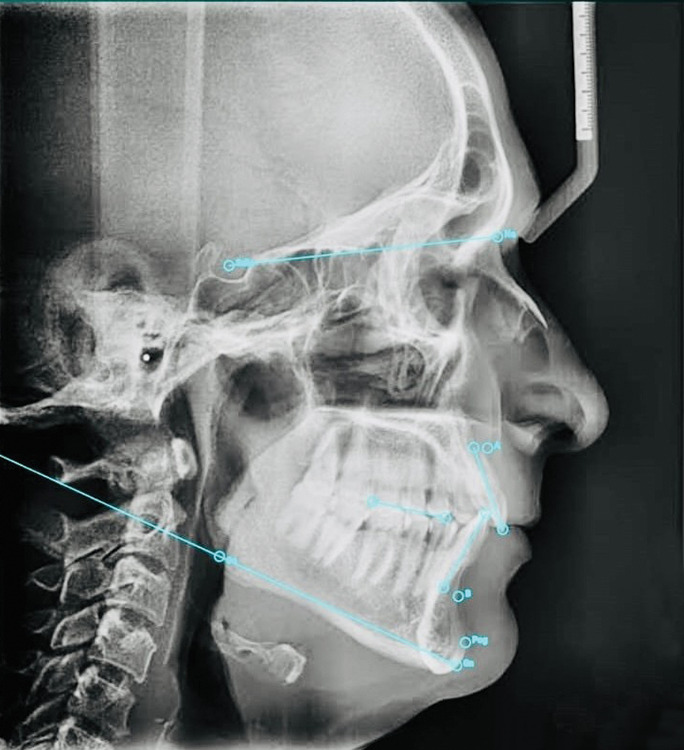

Materials and methods: About 30 pretreatment lateral cephalograms of patients exhibiting mouth-breathing habits, who reported to the dental clinic/institute for various treatment purposes, were selected for study. Digital cephalograms were imported into EasyCeph application and Vistadent software for on-screen digitization. Additionally, manual tracings were performed using acetate sheets, 0.7 mm pencil, ruler, and LED-illuminated tracing board. After ensuring image standardization and calibration, 25 commonly referenced anatomical landmarks were identified on each cephalogram. A total of 22 cephalometric parameters from Steiner's, Tweed's, and Down's analyses were assessed. Descriptive statistics and one-way ANOVA were applied for data analysis.

Results: Linear and angular measurements obtained through digital cephalometric analysis were found to be comparable to those derived from manual tracing methods. Differences observed among the three groups were statistically nonsignificant (p ≤ 0.05).

Conclusion: Digital measurements obtained using EasyCeph and Vistadent software closely aligned with those from the manual tracing method for the majority of clinically relevant parameters. Hence, both EasyCeph and Vistadent can be considered reliable and effective alternatives to traditional manual cephalometric analysis.